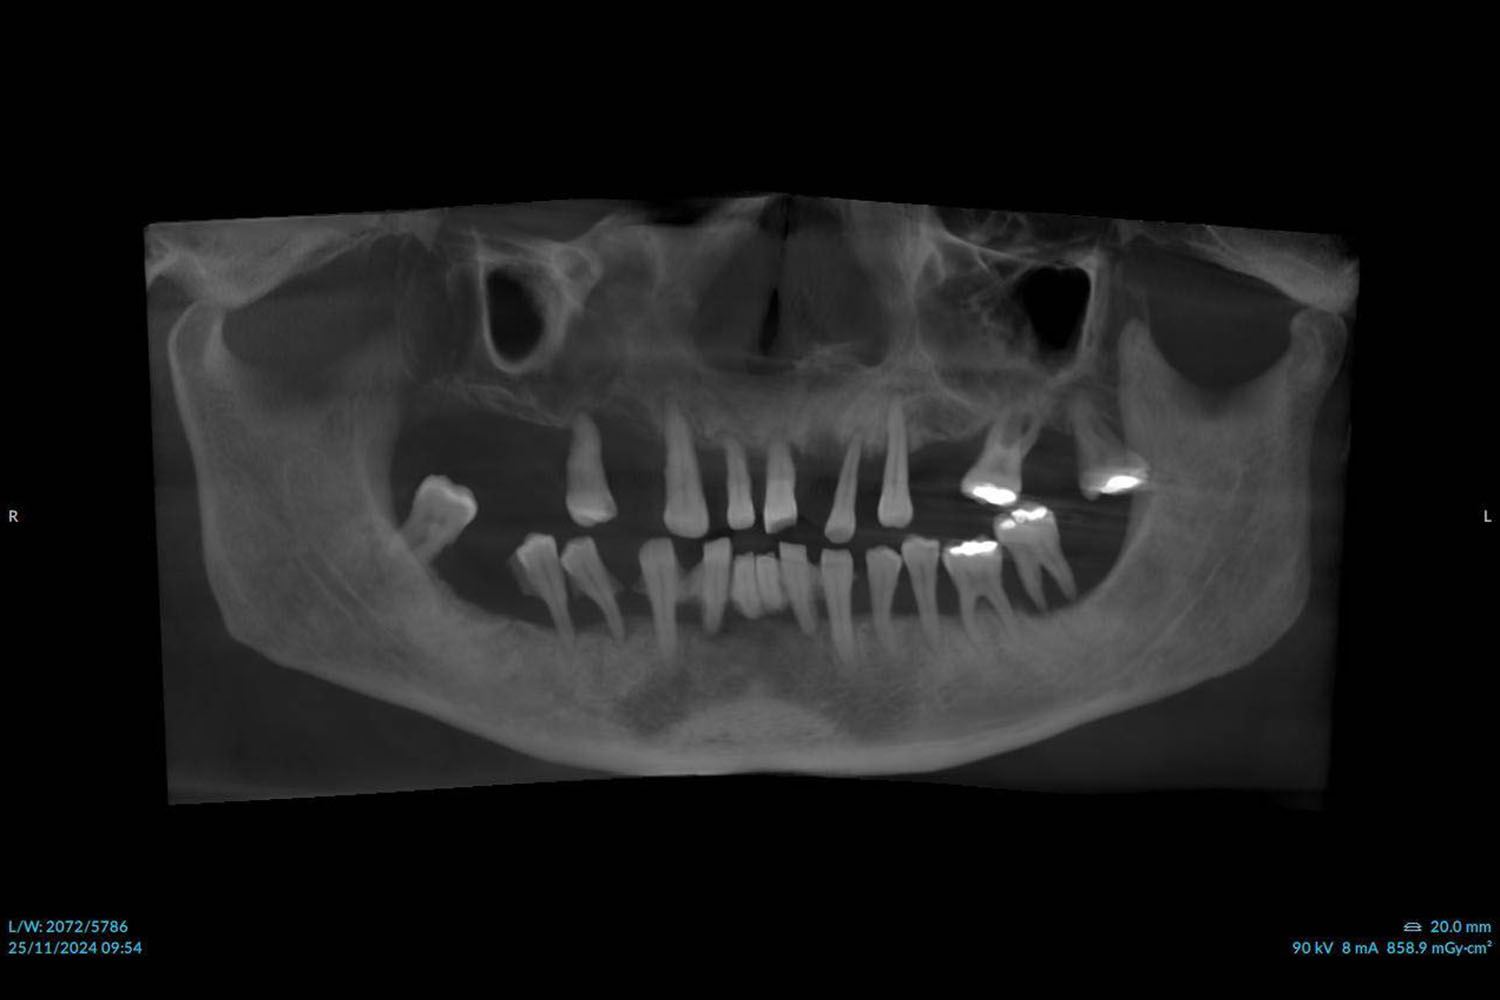

Precizno planiranje uz 3D dijagnostiku

Koristimo suvremenu 3D CBCT dijagnostiku, digitalne otiske i virtualno planiranje implantata kako bismo terapiju planirali precizno i sigurno.